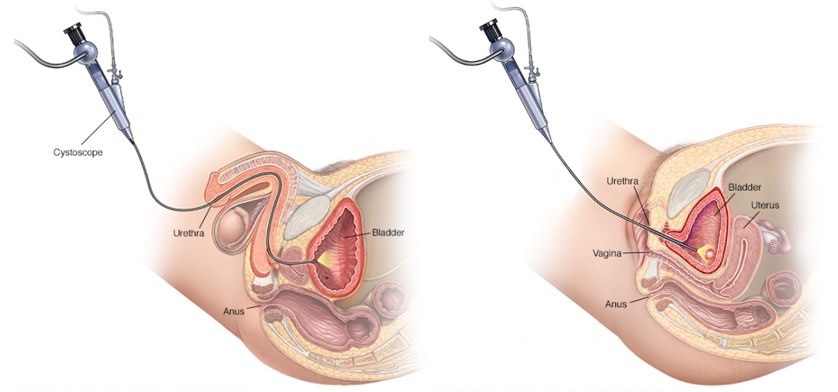

- 1902057: Uretrotomía interna endoscópica.

- 1902062: Uretrocistoscopía.